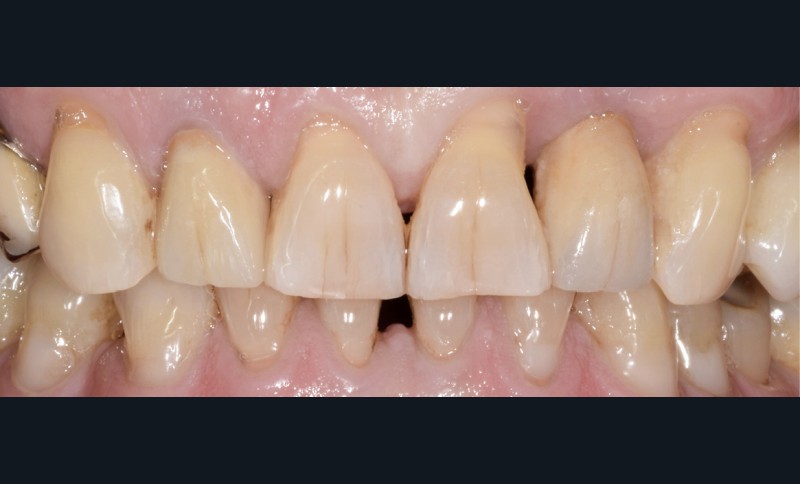

Un patient de 62 ans se présente en consultation afin de réaliser les coiffes prothétiques des dents 12 et 22. La 12 présente une restauration par prothèse transitoire non adaptée. Un implant au niveau de la 22 a été posé par un autre praticien selon une technique chirurgicale en deux temps. Le praticien a adressé le patient pour la réalisation prothétique. L’option de bridge collé cantilever mono ailette n’avait pas été retenue ou proposée selon une technique chirurgicale en deux temps. Le patient souhaite rétablir l’esthétique et la fonction de ces deux dents uniquement.

Au vu des conditions initiales, il nous apparaît impossible de restaurer une esthétique satisfaisante, notamment au niveau de l’alignement des collets, sans une chirurgie muco-gingivale associée à une réhabilitation des dents antérieures par facettes. En effet, la perte de la 22, associée à une forme triangulaire des dents, a provoqué un non-alignement des collets ainsi que la présence de trous noirs entre les dents 21-22 et 22-23. Cependant, les contraintes exprimées par le patient contre-indiquaient ce traitement.